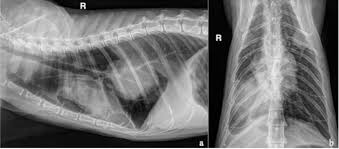

Bone Marrow Cancer Myeloma In Dogs Petmd from www.petmd.com They can cause much more pronounced gastrointestinal distress and affect the bone marrow and immune system putting patients at risk for dangerous infections. The common causes of bone marrow cancer in cats include: Bone tumors can involve either the appendicular (limbs) or axial (spine, ribs, pelvis, scapula, and skull) skeleton. In some cats, bone marrow sampling may need to be repeated in order to see if the bone marrow is responding normally or not. Lymphoma is found to be responsible for around 90 percent of blood cancers and account for about 33 percent of all tumors in cats. Other factors suspected to increase rates of feline cancer include toxins from the environment, passive smoking, excessive grooming, or licking parts of the body that have been in contact with an environmental toxin. Osteosarcoma accounts for 70% of feline bone tumors. Diagnosis of bone cancer in cats there are many key diagnostic tests to positively detect if cancer is present.

While the causes of cancer in cats are unknown, feline leukemia virus is suspected to be a prime contributor. It is a very aggressive tumor that causes lysis (disintegration of the bone), bone production, or both. Feline bone cancer is one of the more common types of cancer in cats, and osteosarcoma is the most common kind of feline bone cancer. A clonal population of cells is a group of cells that have descended from a single cell; Lymphoma is found to be responsible for around 90 percent of blood cancers and account for about 33 percent of all tumors in cats. It is a tumor that often affects the long bones. It occurs in cats and several other species. Bone tumors can involve either the appendicular (limbs) or axial (spine, ribs, pelvis, scapula, and skull) skeleton. Osteosarcoma accounts for 70% of feline bone tumors. In some cats, bone marrow sampling may need to be repeated in order to see if the bone marrow is responding normally or not. Middle aged to older dogs and cats are most commonly affected. For this reason, cats that suffer from anemia caused by lead poisoning or feline leukemia are in a very dangerous situation. During hospitalization, your veterinarian will monitor your cat's progress on a daily basis.